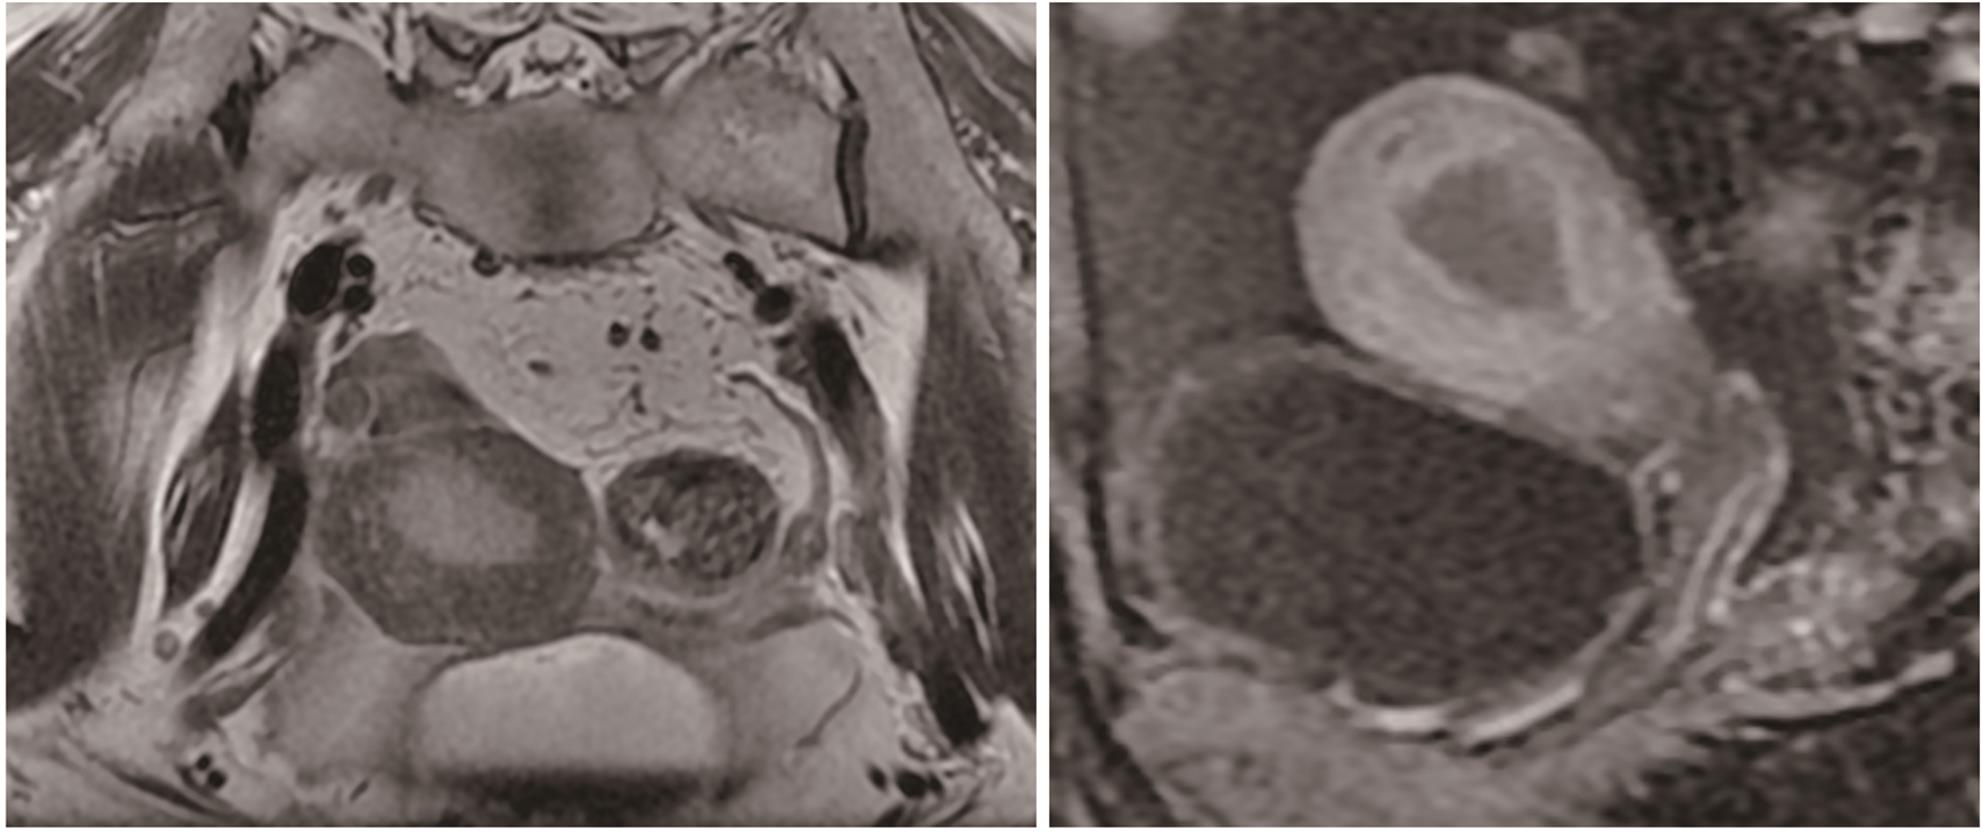

病例报告

失代偿期肝硬化合并多原发癌1例报告

晁文婷, 黄睿

2024, 40(9): 1868-1872. DOI: 10.12449/JCH240923

摘要(912) HTML (383) PDF (1776KB)(105)

摘要:

多原发癌是指在同一个体中存在一种以上的具有不同组织学和部位的癌症,临床较为罕见。本文报告1例肝硬化失代偿期合并多原发癌的病例,主要讨论了肝硬化失代偿期患者合并多原发癌的诊治经过及临床启示。